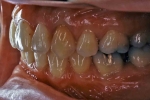

初診時